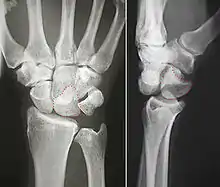

The lunate bone (semilunar bone) is a carpal bone in the human hand. It is distinguished by its deep concavity and crescentic outline. It is situated in the center of the proximal row carpal bones, which lie between the ulna and radius and the hand. The lunate carpal bone is situated between the lateral scaphoid bone and medial triquetral bone.

The lunate is a crescent-shaped carpal bone found within the hand. The lunate is found within the proximal row of carpal bones. Proximally, it abuts the radius. Laterally, it articulates with the scaphoid, medially with the triquetral, and distally with the capitate. The lunate also articulates on its distal and medial surface with the hamate bone.[1]:708[2]

The proximal surface of the lunate bone is smooth and convex, articulating with the radius. The lateral surface is flat and narrow, with a crescentic facet for articulation with the scaphoid. The medial surface possesses a smooth and quadrilateral facet for articulation with the triquetral. The palmar surface is rough, as is the dorsal surface. The dorsal surface is broad and rounded. The distal surface of the bone is deep and concave.[3]